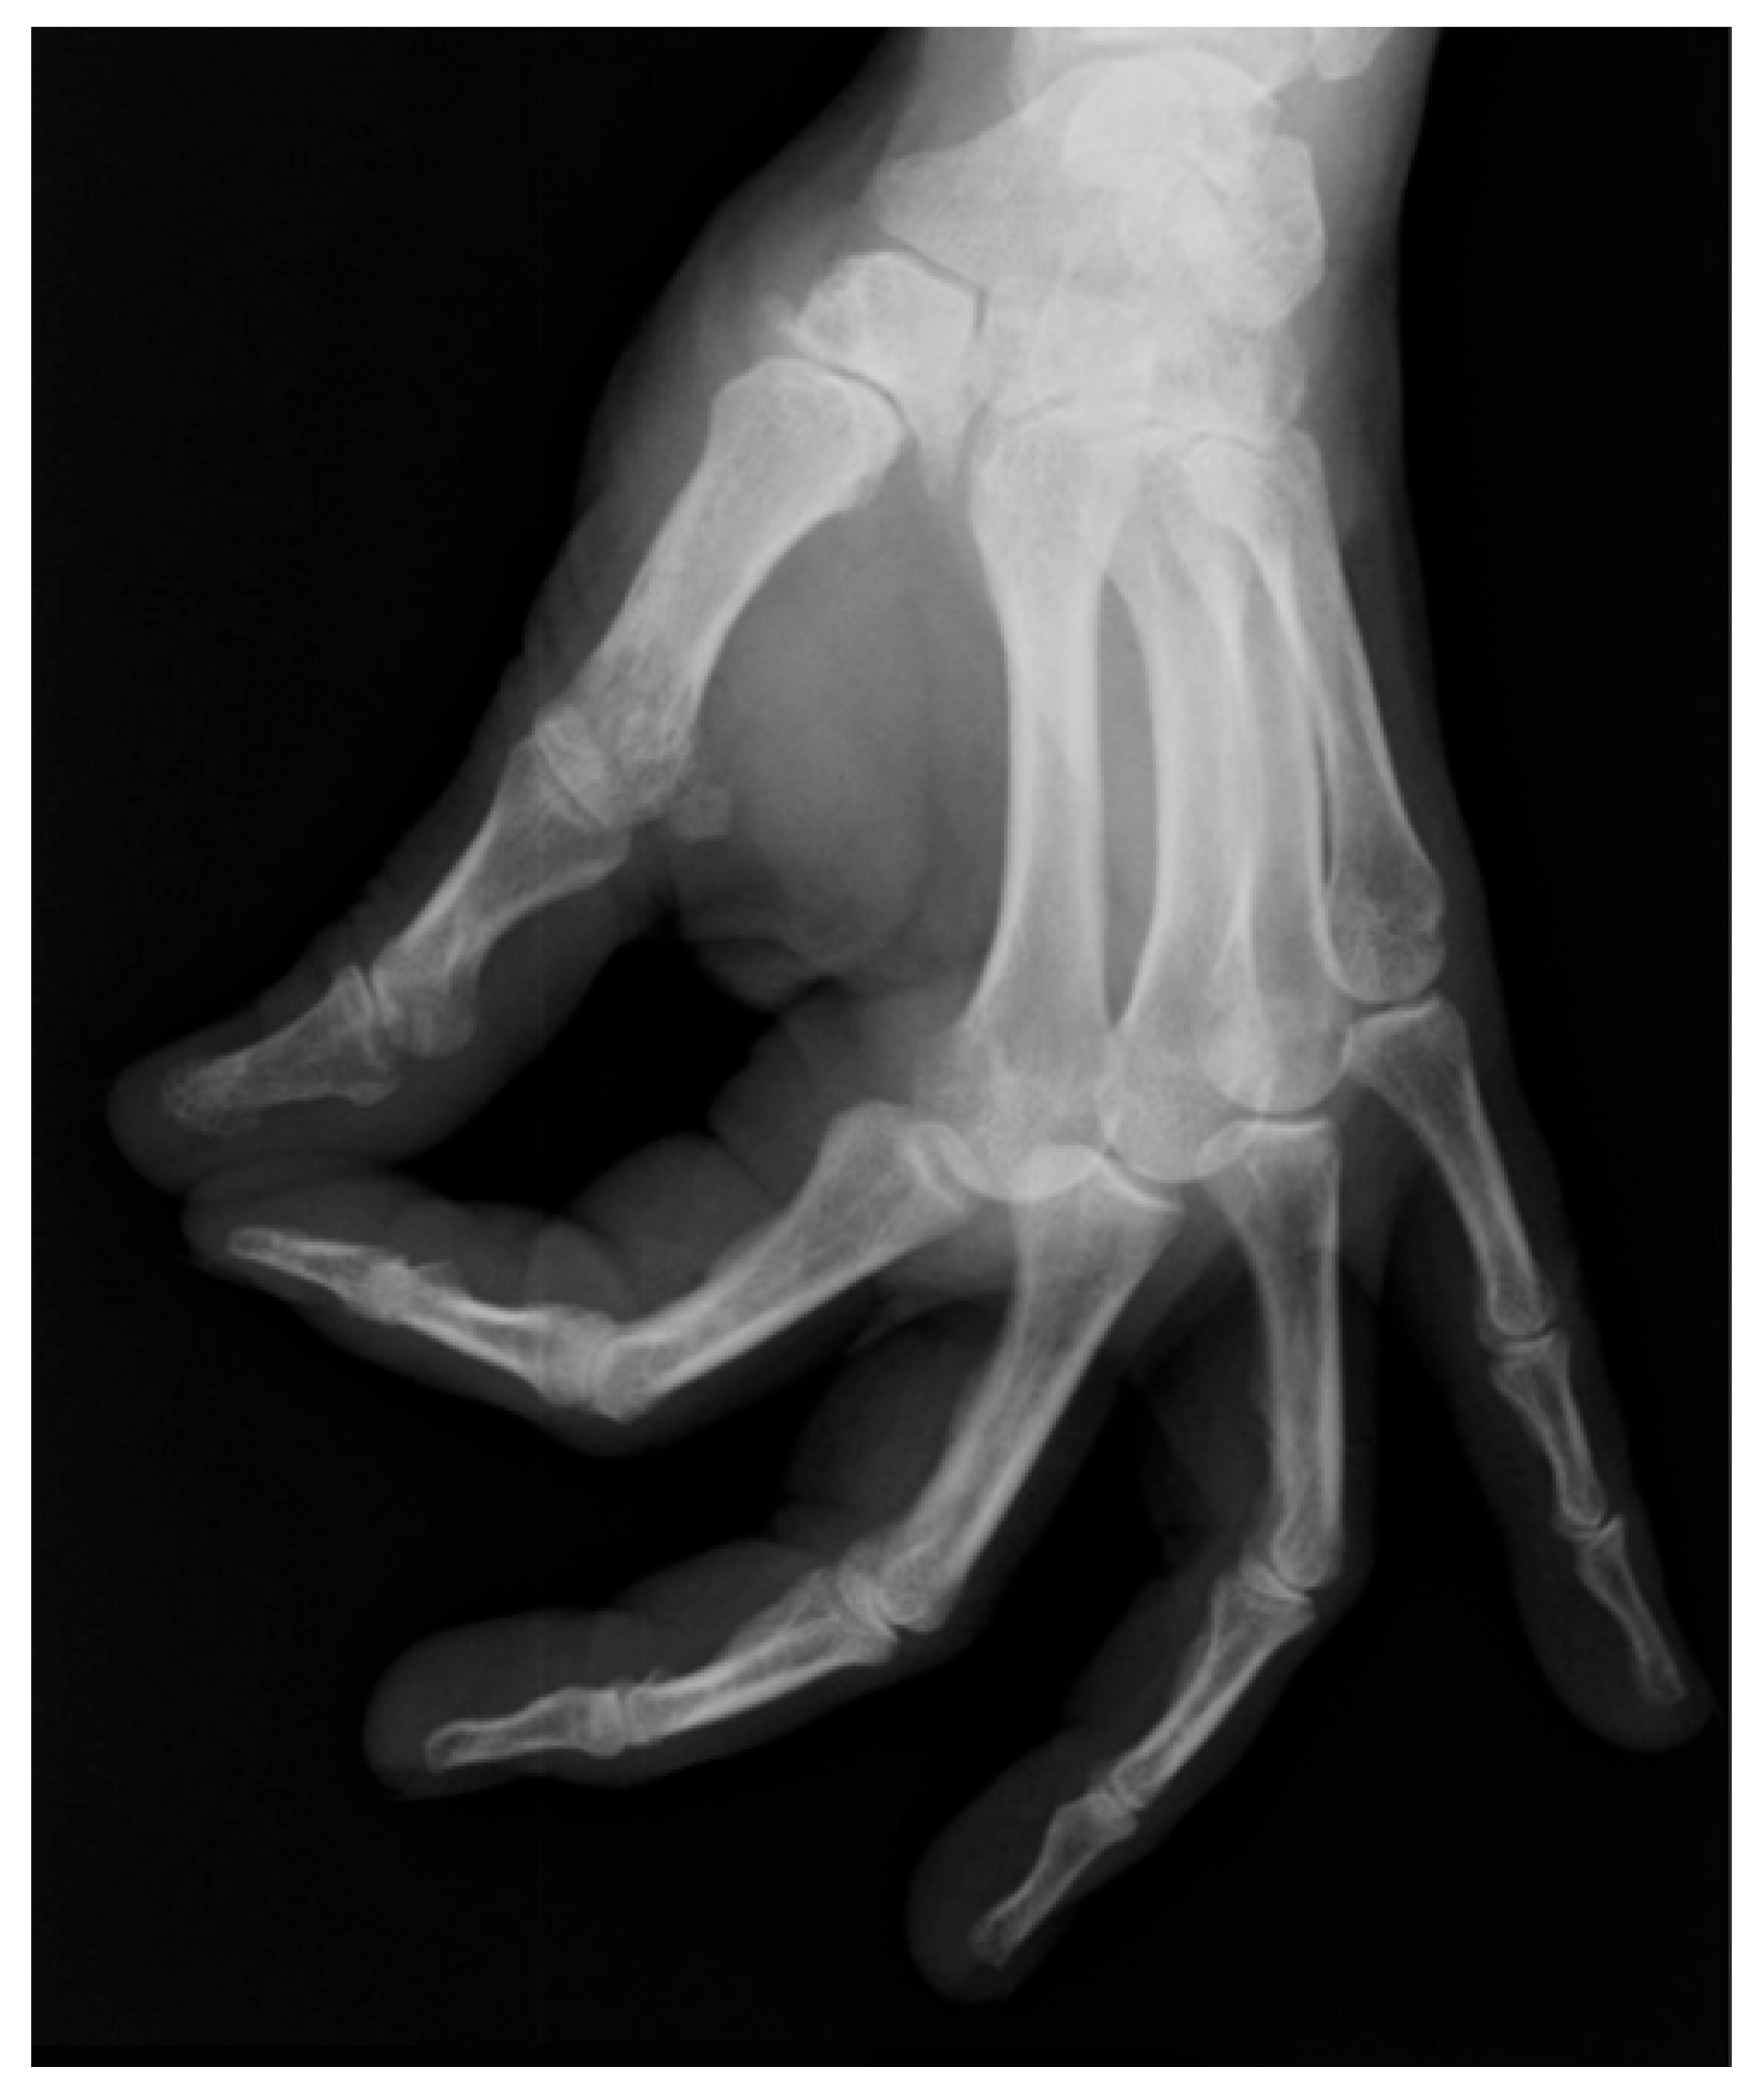

3.3. Type of Prosthesis